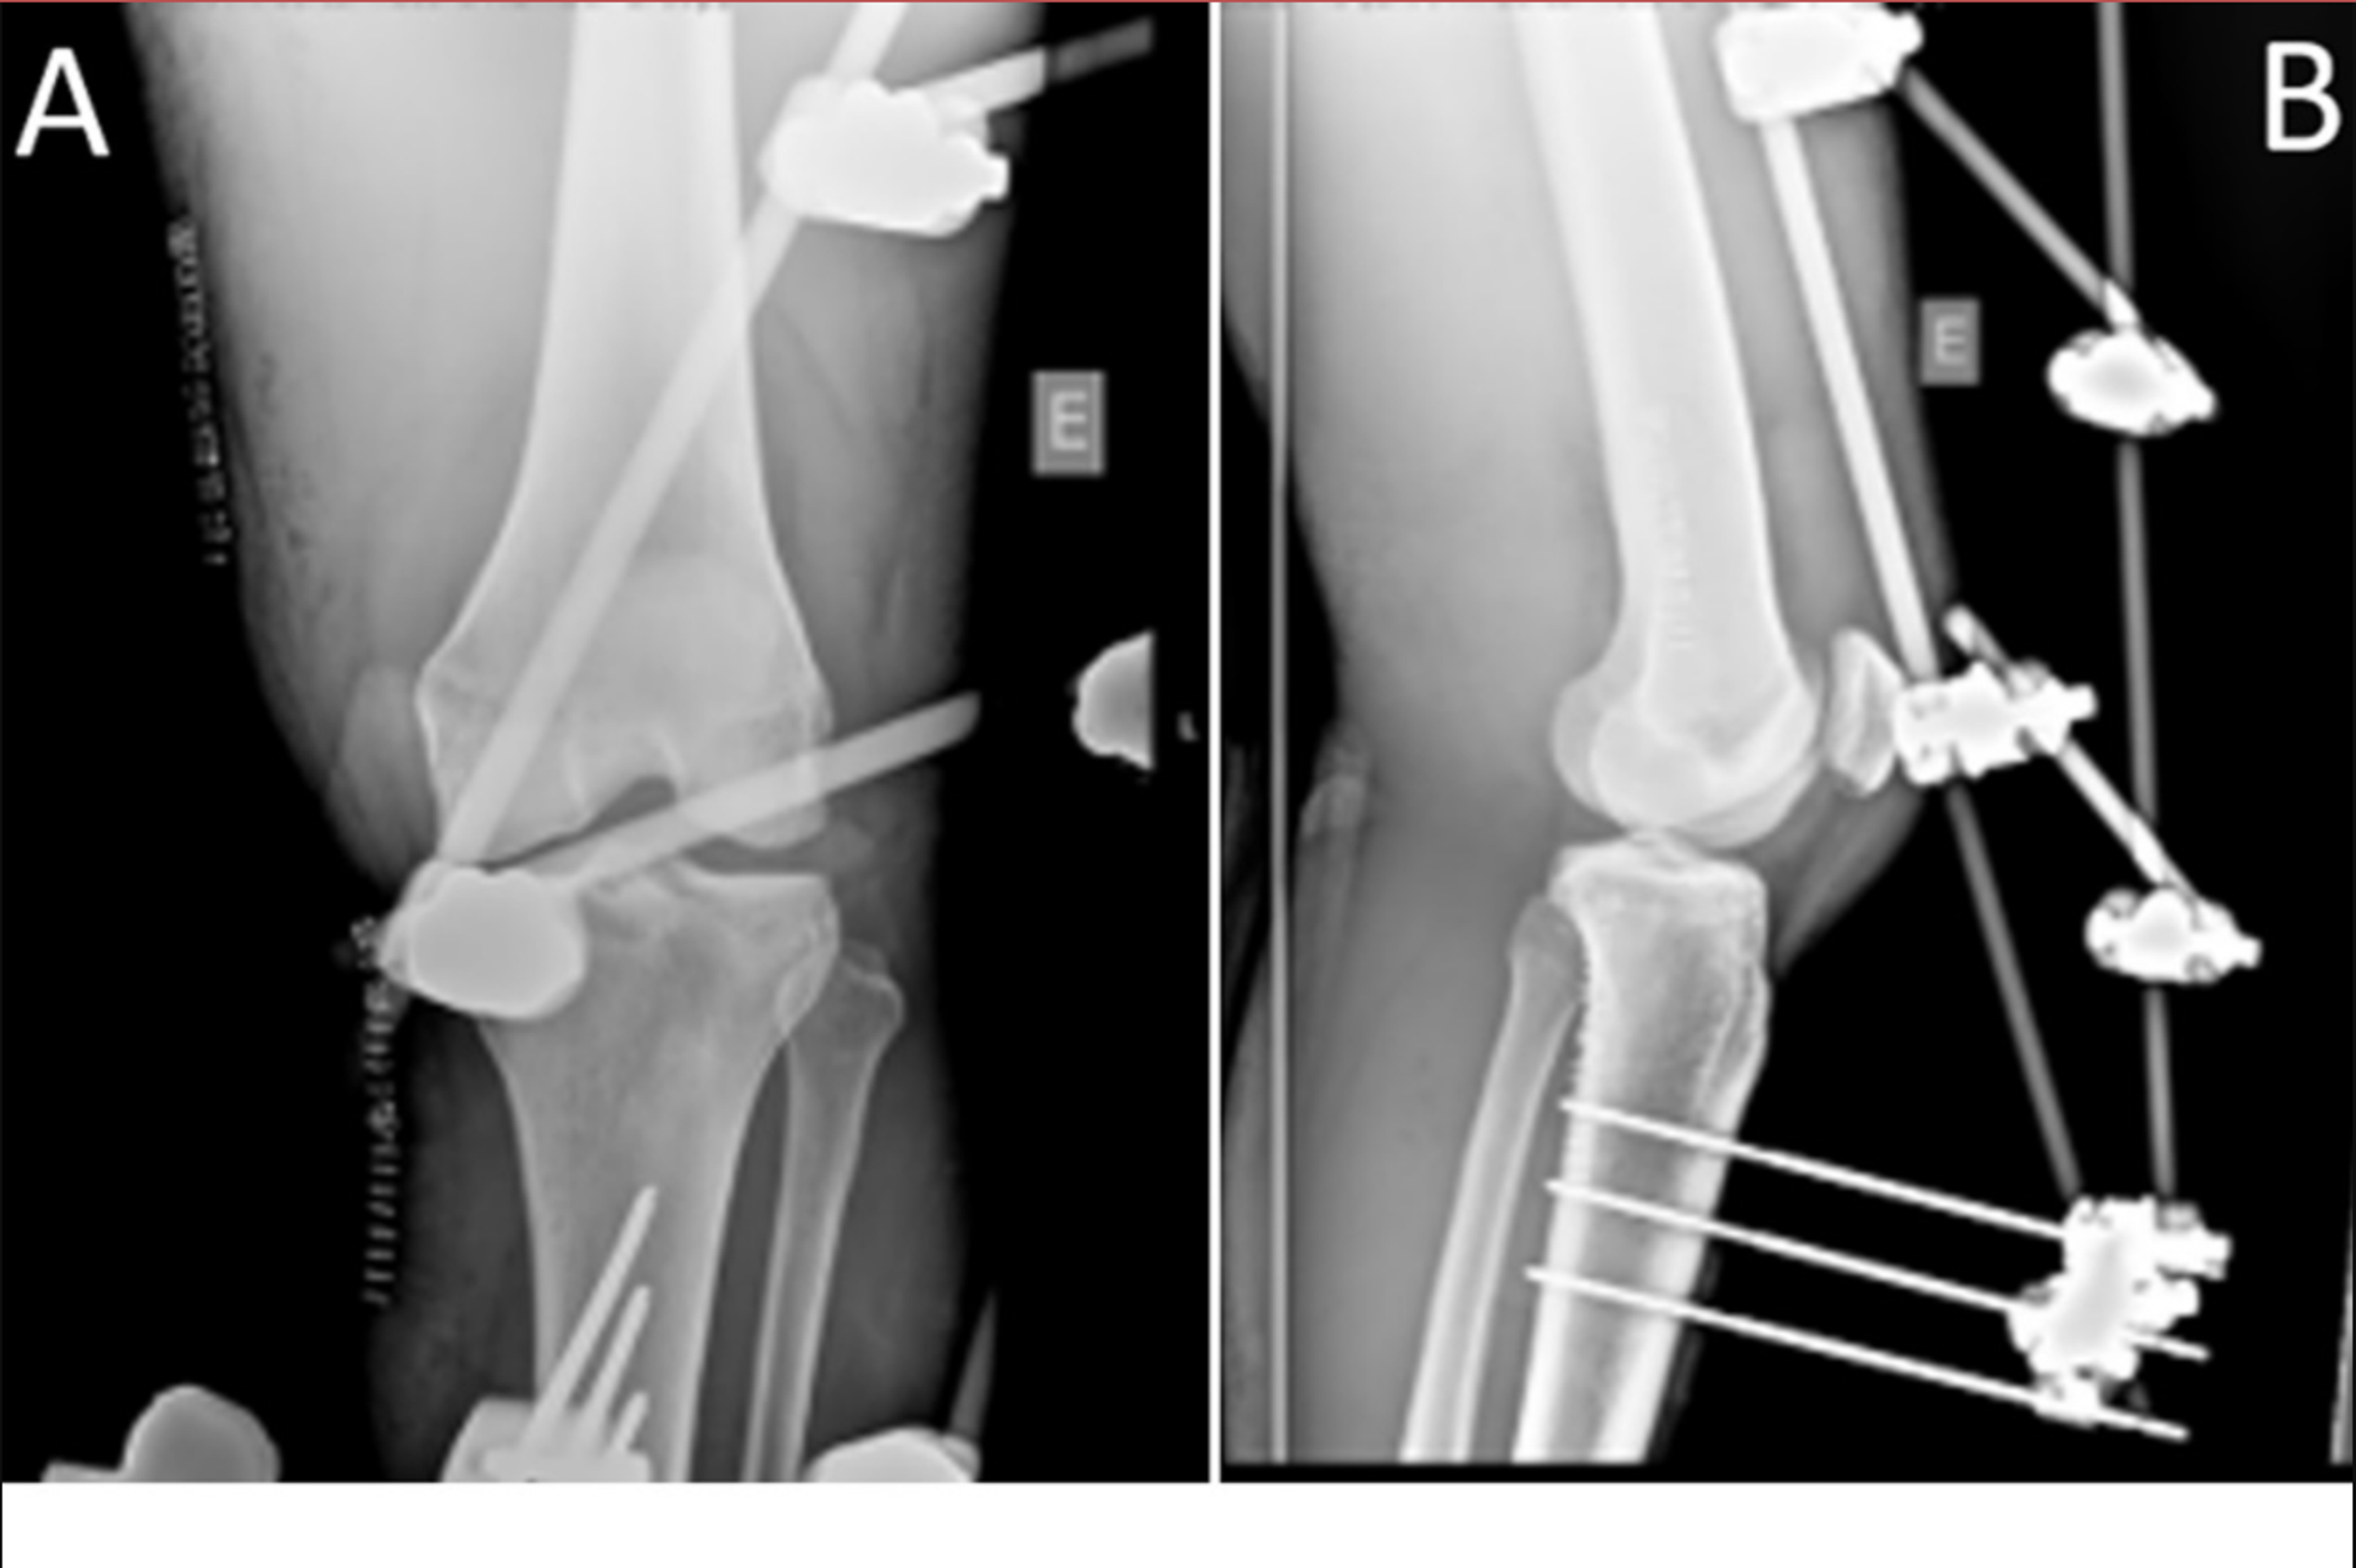

High tibial osteotomy with external fixator. A and B Before correction Cast After External Fixator An external fixator is a surgical device that allows a fractured or misaligned bone to heal properly. An external fixator is a stabilizing frame to hold the broken bones in proper position. Primary issues in the immediate postoperative period while still in the hospital setting include wound and wire/pin care, appropriate antibiosis, pain management,. By adding pins in different planes.. Cast After External Fixator.